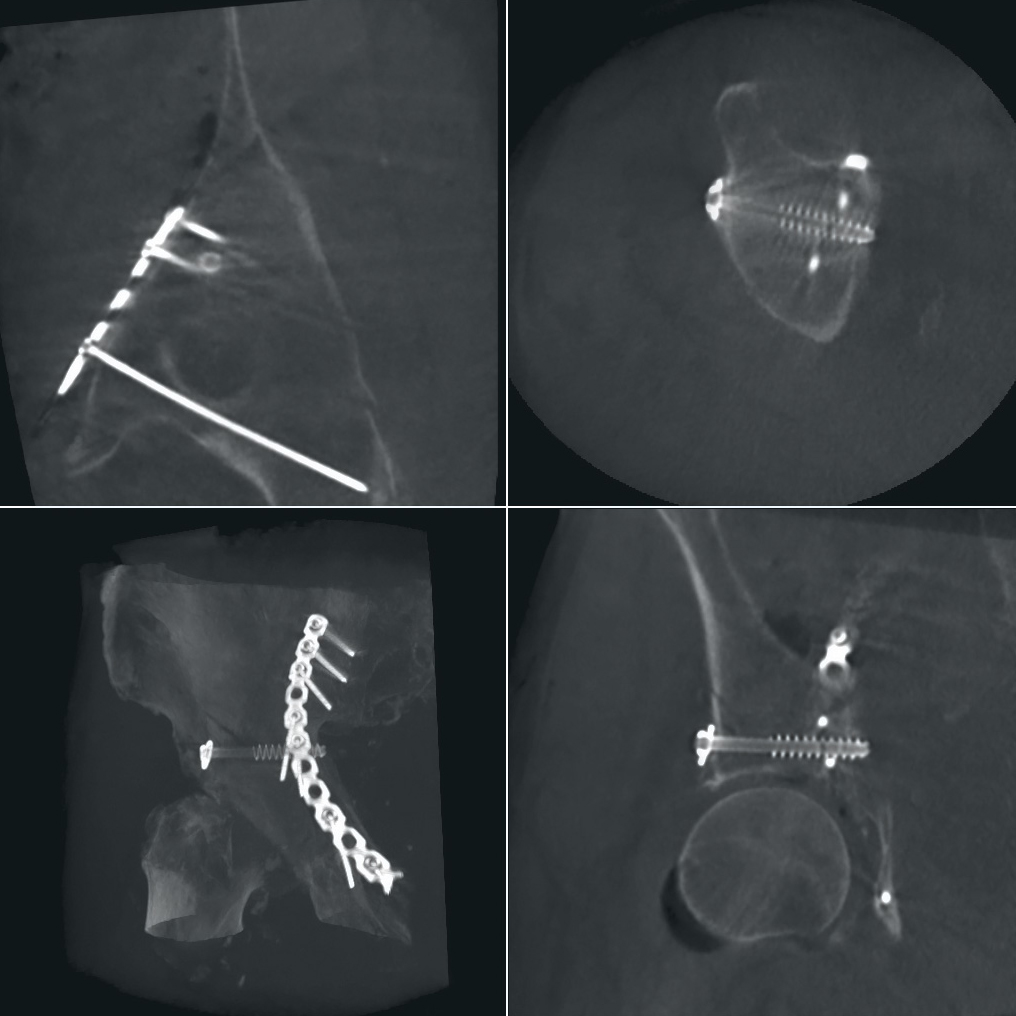

Orthopedics and Traumatology